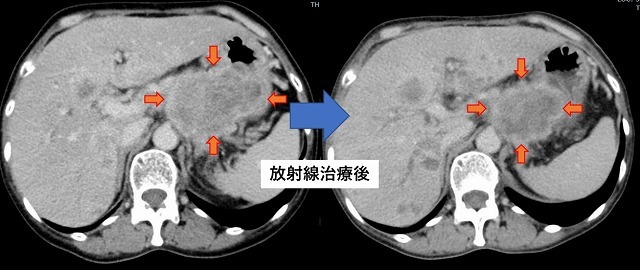

転移性肝腫瘍・単回照射

乳がん多発肝転移。

肝臓内に転移巣が多発して肝腫大をきたし、腹痛や黄疸を伴っている。

肝臓全体に1回限りの放射線治療を行うことで症状改善が得られた。

報告では6~7割の方で症状改善が得られる。